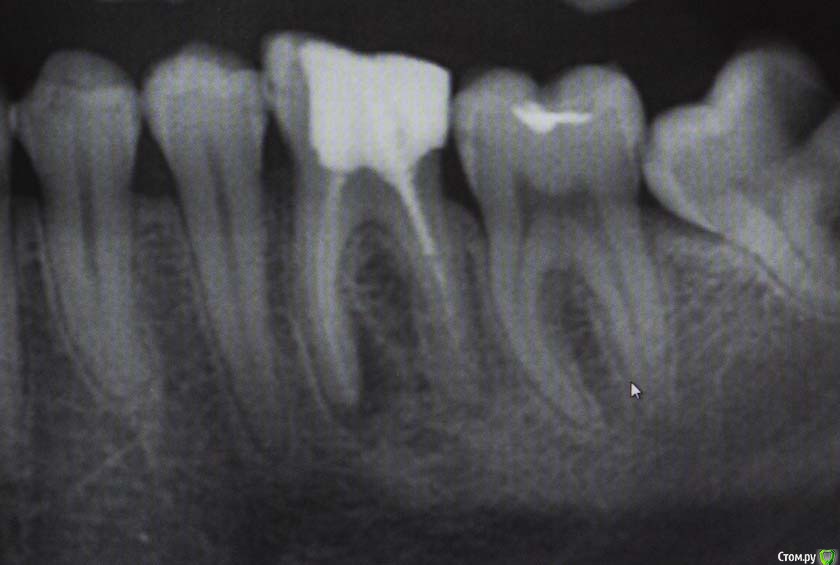

M@estro Опубликовано 9 июля, 2015 Автор Поделиться Опубликовано 9 июля, 2015 Тоже подниму тему. Травму отрицает, жалобы на потемнение. Витальность "-", перкуссия "-" , на рентгене подсказка - есть латераль. Вперёд, мыть ! 60 апекс, гибрид паковка. 1 час с пломбой 7 Ссылка на комментарий

M@estro Опубликовано 23 июля, 2015 Автор Поделиться Опубликовано 23 июля, 2015 И сюда закину Жалобы на боли, КЕСТУ и желание " удалить " . Зуб 3.6 . Пациент - парнишка 16 лет. Зуб ранее пытались лечить,парень признался, что было больно, и больше он туда не вернулся, а в другой клинике предложили удалить зуб , ибо "кЕста". Перкуссия - резко-болезненна , в полости зуба - остатки ватки. В первое посещение - билд, обработка каналов ( дистальный 70/02 , медиальные 50 / 02) , антисептика, кальций на 2 недели . Второе посещение - обтурация , в дистальном -" неаккуратненько", плюнул силер. Следом бюджетная мк коронка. Контрольный через 4 месяца. 9 Ссылка на комментарий

M@estro Опубликовано 27 января, 2016 Автор Поделиться Опубликовано 27 января, 2016 Повторное эндо ( ре-колл 7 месяцев) . 5 каналов в 3.6 . Обтурация - CWCT . Мех.обработка - Profile + m2 . Ca(OH)2 на 2 недели 12 Ссылка на комментарий